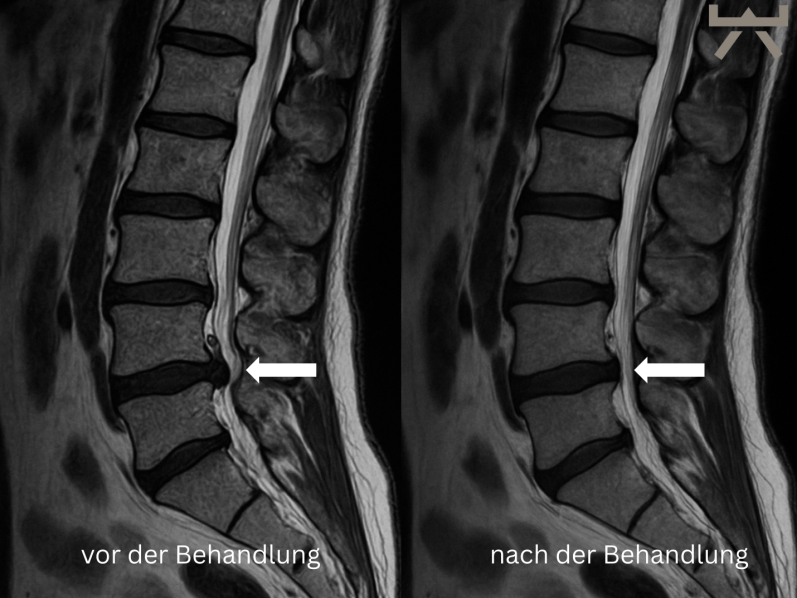

Zunächst einmal die gute Nachricht: Unser Körper ist dazu fähig ca. 2/3 aller Bandscheibenvorfälle selbständig aufzulösen (siehe das Bild hier unten)! Kurioserweise heilen ausgeprägtere Bandscheibenvorfälle besser als kleinere. Studien zeigen keinen Mehrwert von einer operativen Therapie in Vergleich zu einer nicht-operativen Therapie. Gleichzeitig spielen grundsätzliche Risiken und Komplikationen, welche bei jeder Operation auftreten können, eine Rolle. Zusätzlich zeigen Untersuchungen der AOK Nordwest und der Techniker, dass 8 von 10 Operationen am Rücken unnötig sind. Darunter zählen auch Bandscheibenoperationen.